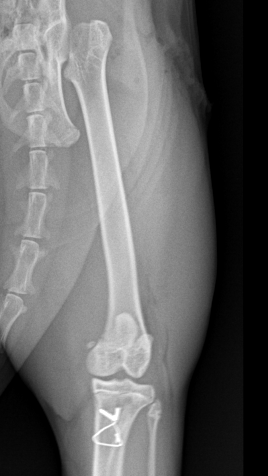

보다 정확한 원인 평가를 위해 본원에서는

방사선(X-ray) 검사를 통한 정밀 진단을 진행했습니다.

정밀 진단 진행 결과

루미(가명)는 양측 슬개골 내측 탈구뿐만 아니라

양측 고관절 아탈구도 함께 확인되었습니다.

이는 무릎 관절과 고관절에서 동시에 통증을 유발할 수 있는 상태로,

슬개골 탈구만 교정할 경우

보행 이상이 완전히 해소되지 않을 가능성이 높은 상황이었습니다.